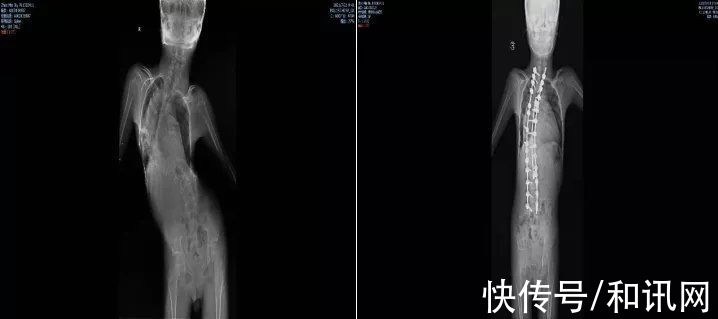

每月第一个周四的下午,都是北大医院MDT团队的会诊时间。2021年,16岁的已经完全丧失行走能力三年的小乐,被确诊为SMAⅢ型,伴有重度脊柱畸形,导致躯体剧烈疼痛和肺功能进一步恶化。

图/手术前后对比图 来源/ 受访者供图

脊柱的扭曲,增加了寻找药物的鞘内注射点,让药物顺利进入到椎管内的难度。儿科接诊后反复与各科室沟通,最终决定让小乐先接受脊柱畸形矫形手术治疗。

2021年9月,李淳德在完成脊柱畸形矫正手术的同时,还要切除部分腰椎椎板,为后面注射药物预留出骨性通道。虽然手术顺利,但术后小乐的腰部无法弯曲,已经没有同正常人一样的解剖标志,预留的通道也很难找到。麻醉科副主任胡晓通过超声引导反复摸索,寻找到预留的骨性通道,最终穿刺成功,完成国内首次SMA脊柱畸形矫形术联合诺西那生鞘内注射。